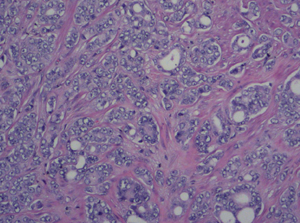

Surgical Pathology

Breast Cancer

Colon-Cancer

Colon Cancer

Malignant Melanoma

Pleural-Fluid-with-Metastatic-Cancer

Pleural Fluid with

Metastatic Cancer

Prostate-Cancer

Prostate Cancers

Soft-Tissue-Sarcoma

Soft Tissue Sarcoma